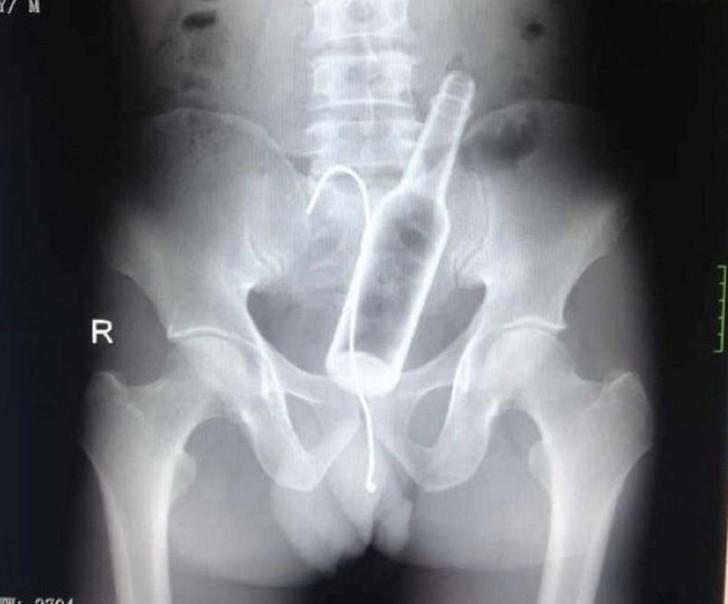

9. Бутылка.